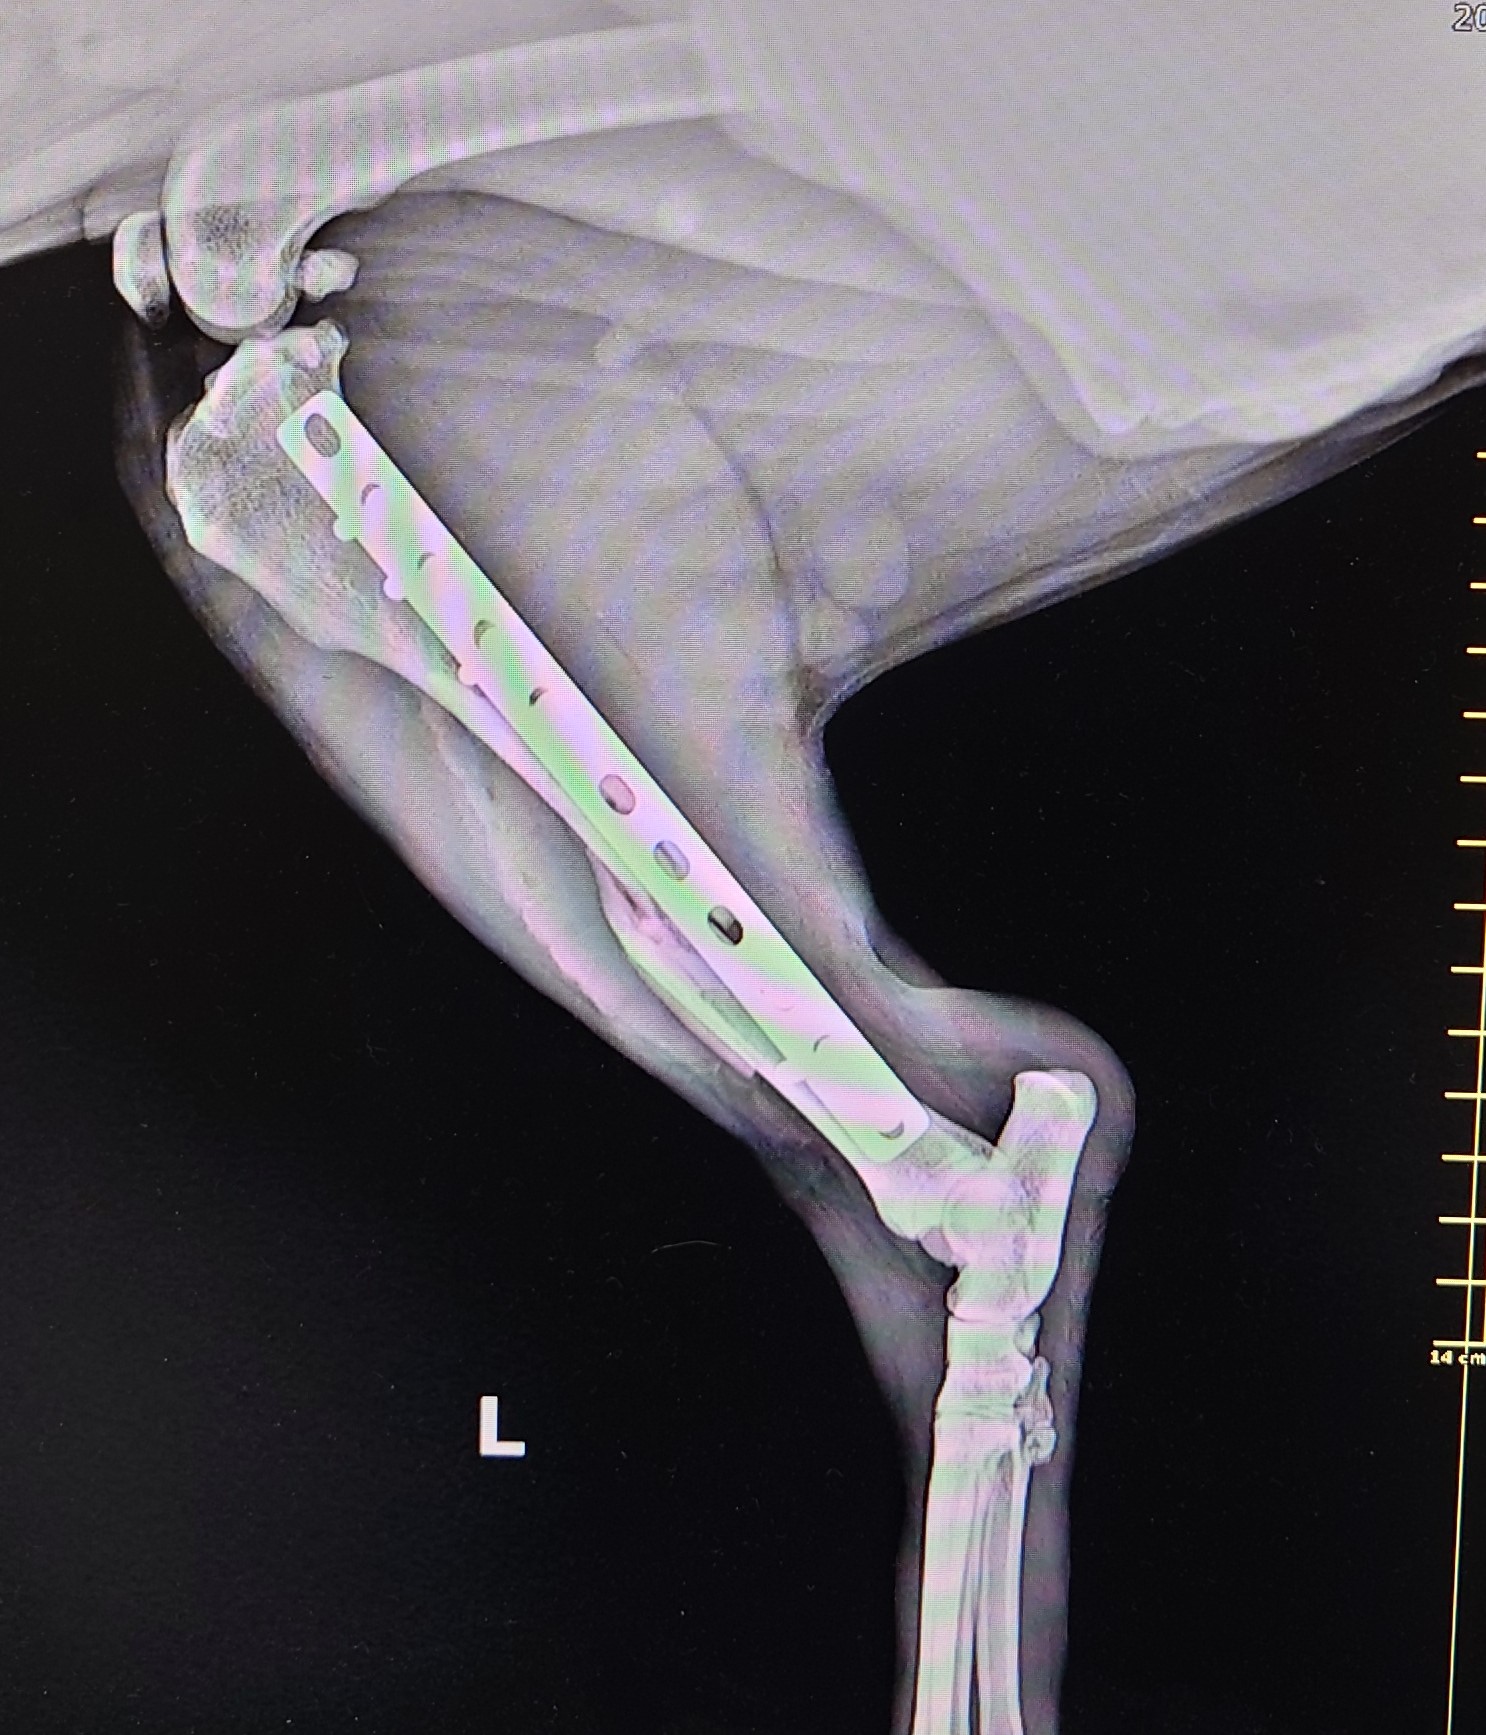

在X光下可以看到他的左後腳脛骨中段粉碎性骨折,還好其他腳沒受傷,還能站立行走。

手術方式選擇用骨板進行復位與固定,在斷端兩側分別打入3-4根骨螺絲進行固定與支撐。後續住院觀察兩日給予止痛藥後就回家照顧了。